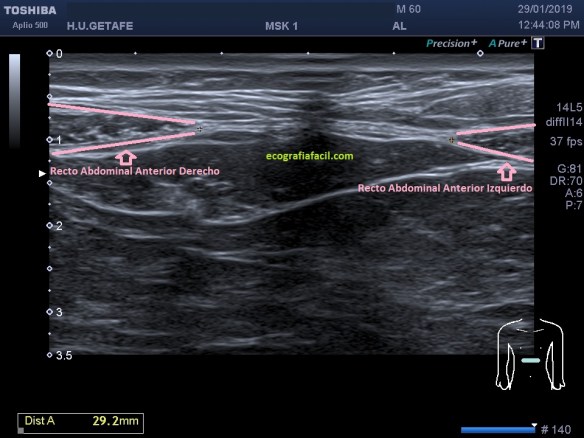

Si tu lo quieres estudiar en un corte transverso o eje corto del tendón verás como muestra de normalidad la imagen número 1. Semiológicamente es muy agradecido. Ves el tendón ovalado, hiperecogénico reposado en la corredera bicipital. El ligamento transverso humeral, hiperecogénico y lineal, anterior a la estructura tendinosa que descansa en la corredera.

Vamos a partir de la normalidad y te vienes a ver ahora la patología que hoy nos ocupa, mira. En ocasiones podemos encontrarnos la imagen patológica que indica luxación del tendón, imagen 2. Es un corte en Eje corto. Ves la corredera bicipital vacía, el tendón fuera de su localización habitual, hacia medial, como es habitual, pero conservando la ecoestructura.